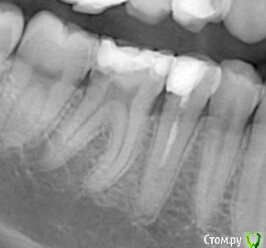

OlgaVeva Опубликовано 15 января, 2019 Поделиться Опубликовано 15 января, 2019 Здравствуйте! Ситуация такая: месяц назад мне запломбировали зуб, нижнюю шестерку справа. Через несколько дней я делала снимки соседнего зуба, и обнаружилось что-то темное в этом зубе (шестерке). Что это значит? Нужно все переделывать или это нормально? Там где темное, как раз была дырка, и ранее этот зуб уже пломбировался. Спасибо. Ссылка на комментарий

St. Опубликовано 15 января, 2019 Поделиться Опубликовано 15 января, 2019 Некоторые материалы могут быть неконтрастными, то есть черные на снимке Ссылка на комментарий